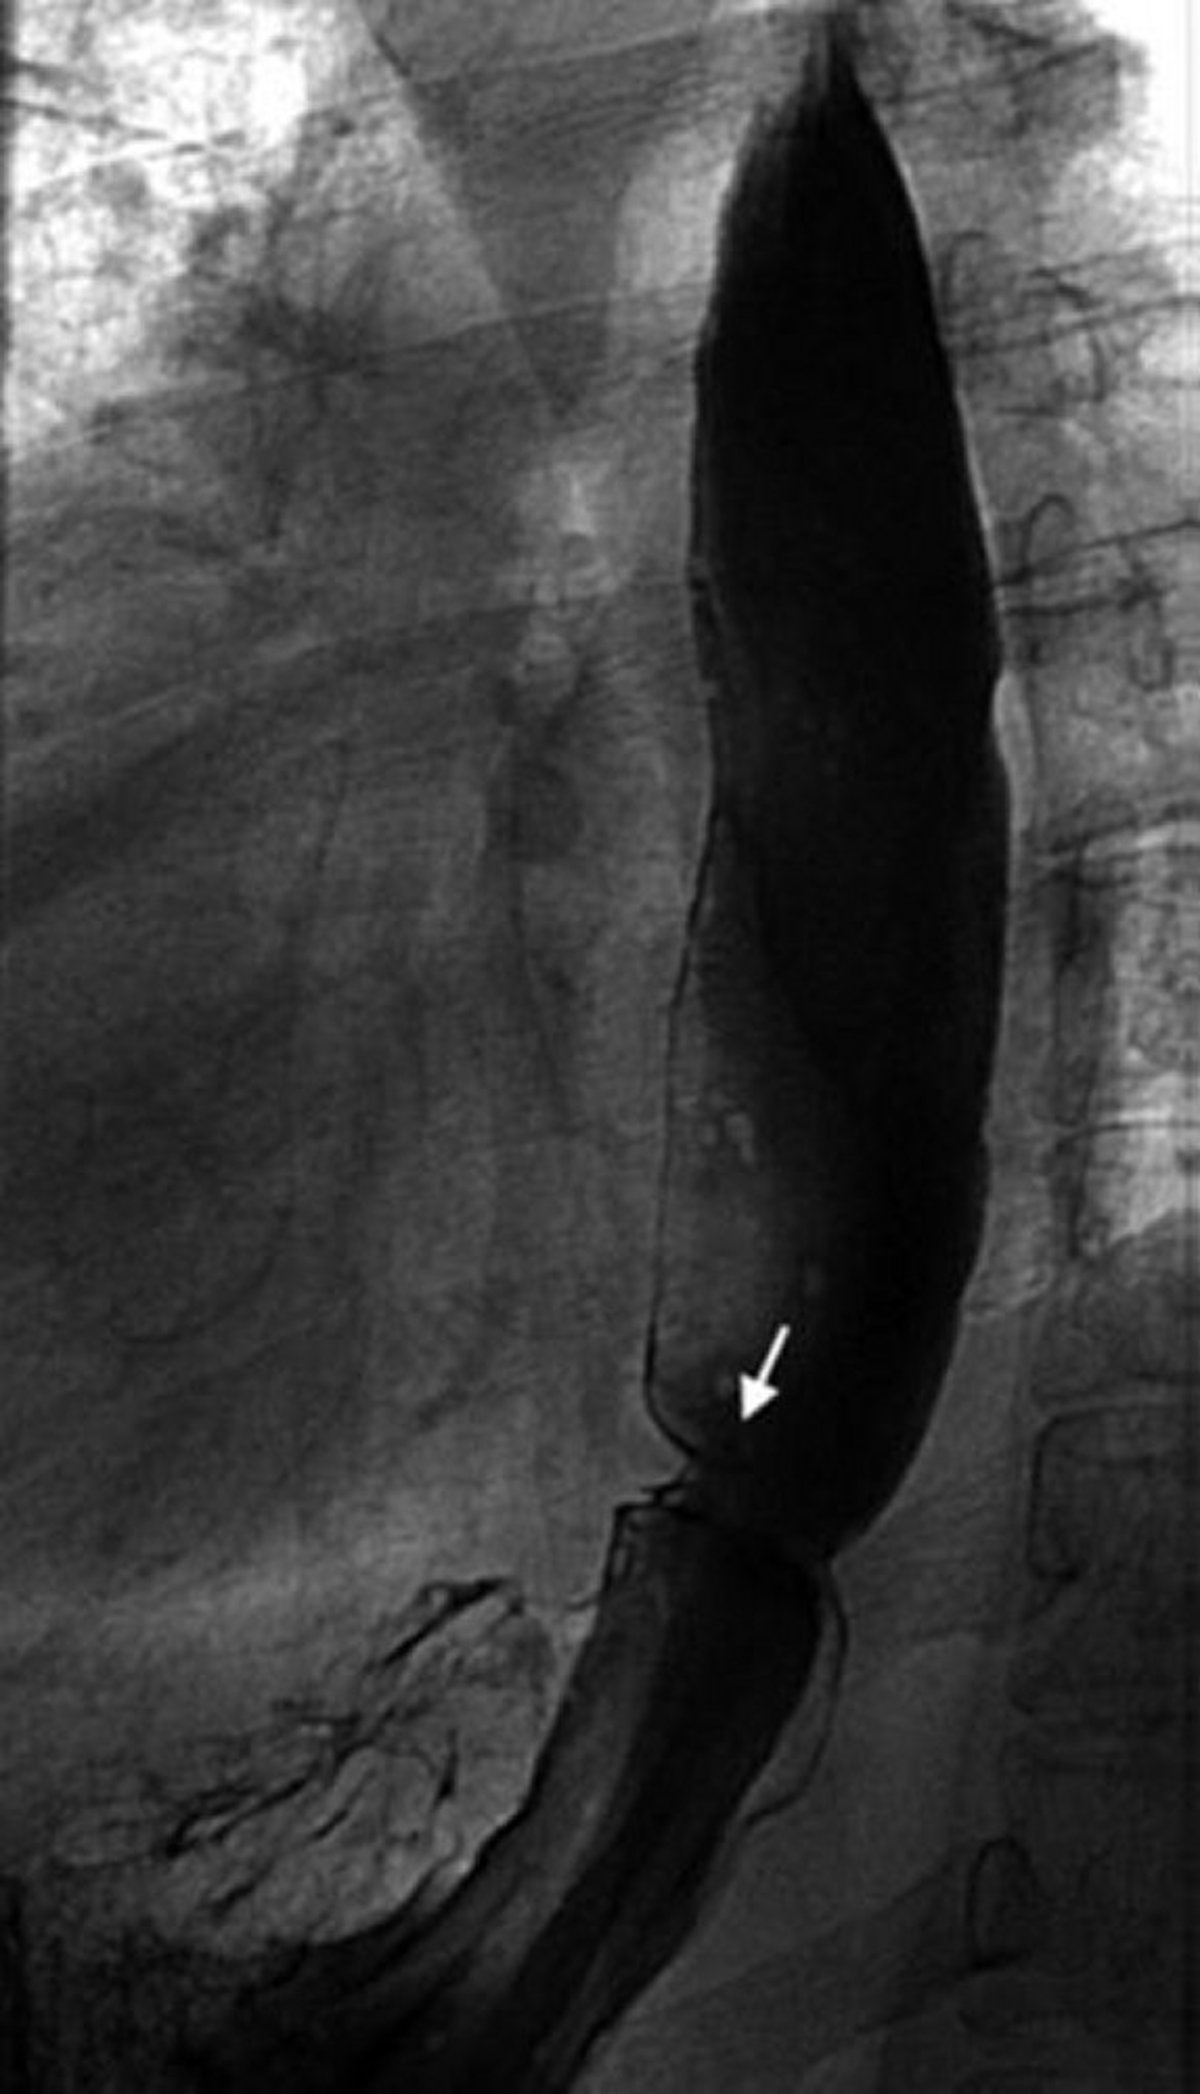

Barium Swallow Showing Esophageal Ring

This image shows a Schatzki ring (arrow).